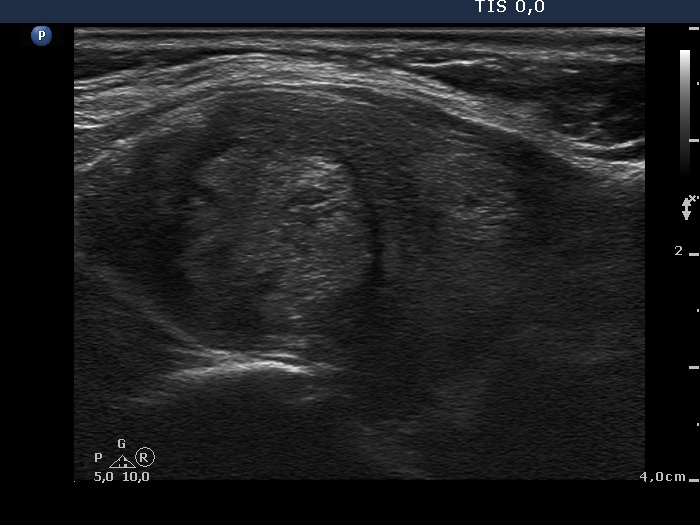

First examination (first and second rows of images):

Ultrasonography. A diffusely hypoechogenic thyroid was found with multiple lesions. There was a hypoechogenic lesion in the dorsal part of the right lobe. This lesion showed taller-than-wide and longer-than-wide shape. The left lobe had two lesions which were more echogenic than the non-nodular part of the lobe, however less echogenic than a normal, healthy thyroid.